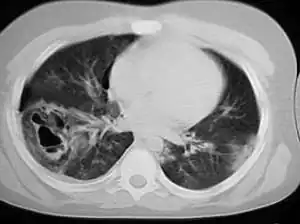

Severe pulmonary contusion with pneumothorax and hemothorax following severe chest trauma[68]

A large amount of force is required to cause pulmonary contusion; a person injured with such force is likely to have other types of injuries as well.[23] In fact, pulmonary contusion can be used to gauge the severity of trauma.[25] Up to three quarters of cases are accompanied by other chest injuries,[39] the most common of these being hemothorax and pneumothorax.[37] Flail chest is usually associated with significant pulmonary contusion,[15] and the contusion, rather than the chest wall injury, is often the main cause of respiratory failure in people with these injuries.[69] Other indications of thoracic trauma may be associated, including fracture of the sternum and bruising of the chest wall.[63] Over half of fractures of the scapula are associated with pulmonary contusion.[27] The contusion is frequently found underlying fracture sites.[35] When accompanied by a fracture, it is usually concentrated into a specific location—the contusion is more diffuse when there is no fracture.[31][43] Pulmonary lacerations may result from the same blunt or penetrating forces that cause contusion.[6] Lacerations can result in pulmonary hematomas; these are reported to develop in 4–11% of pulmonary contusions.[6]